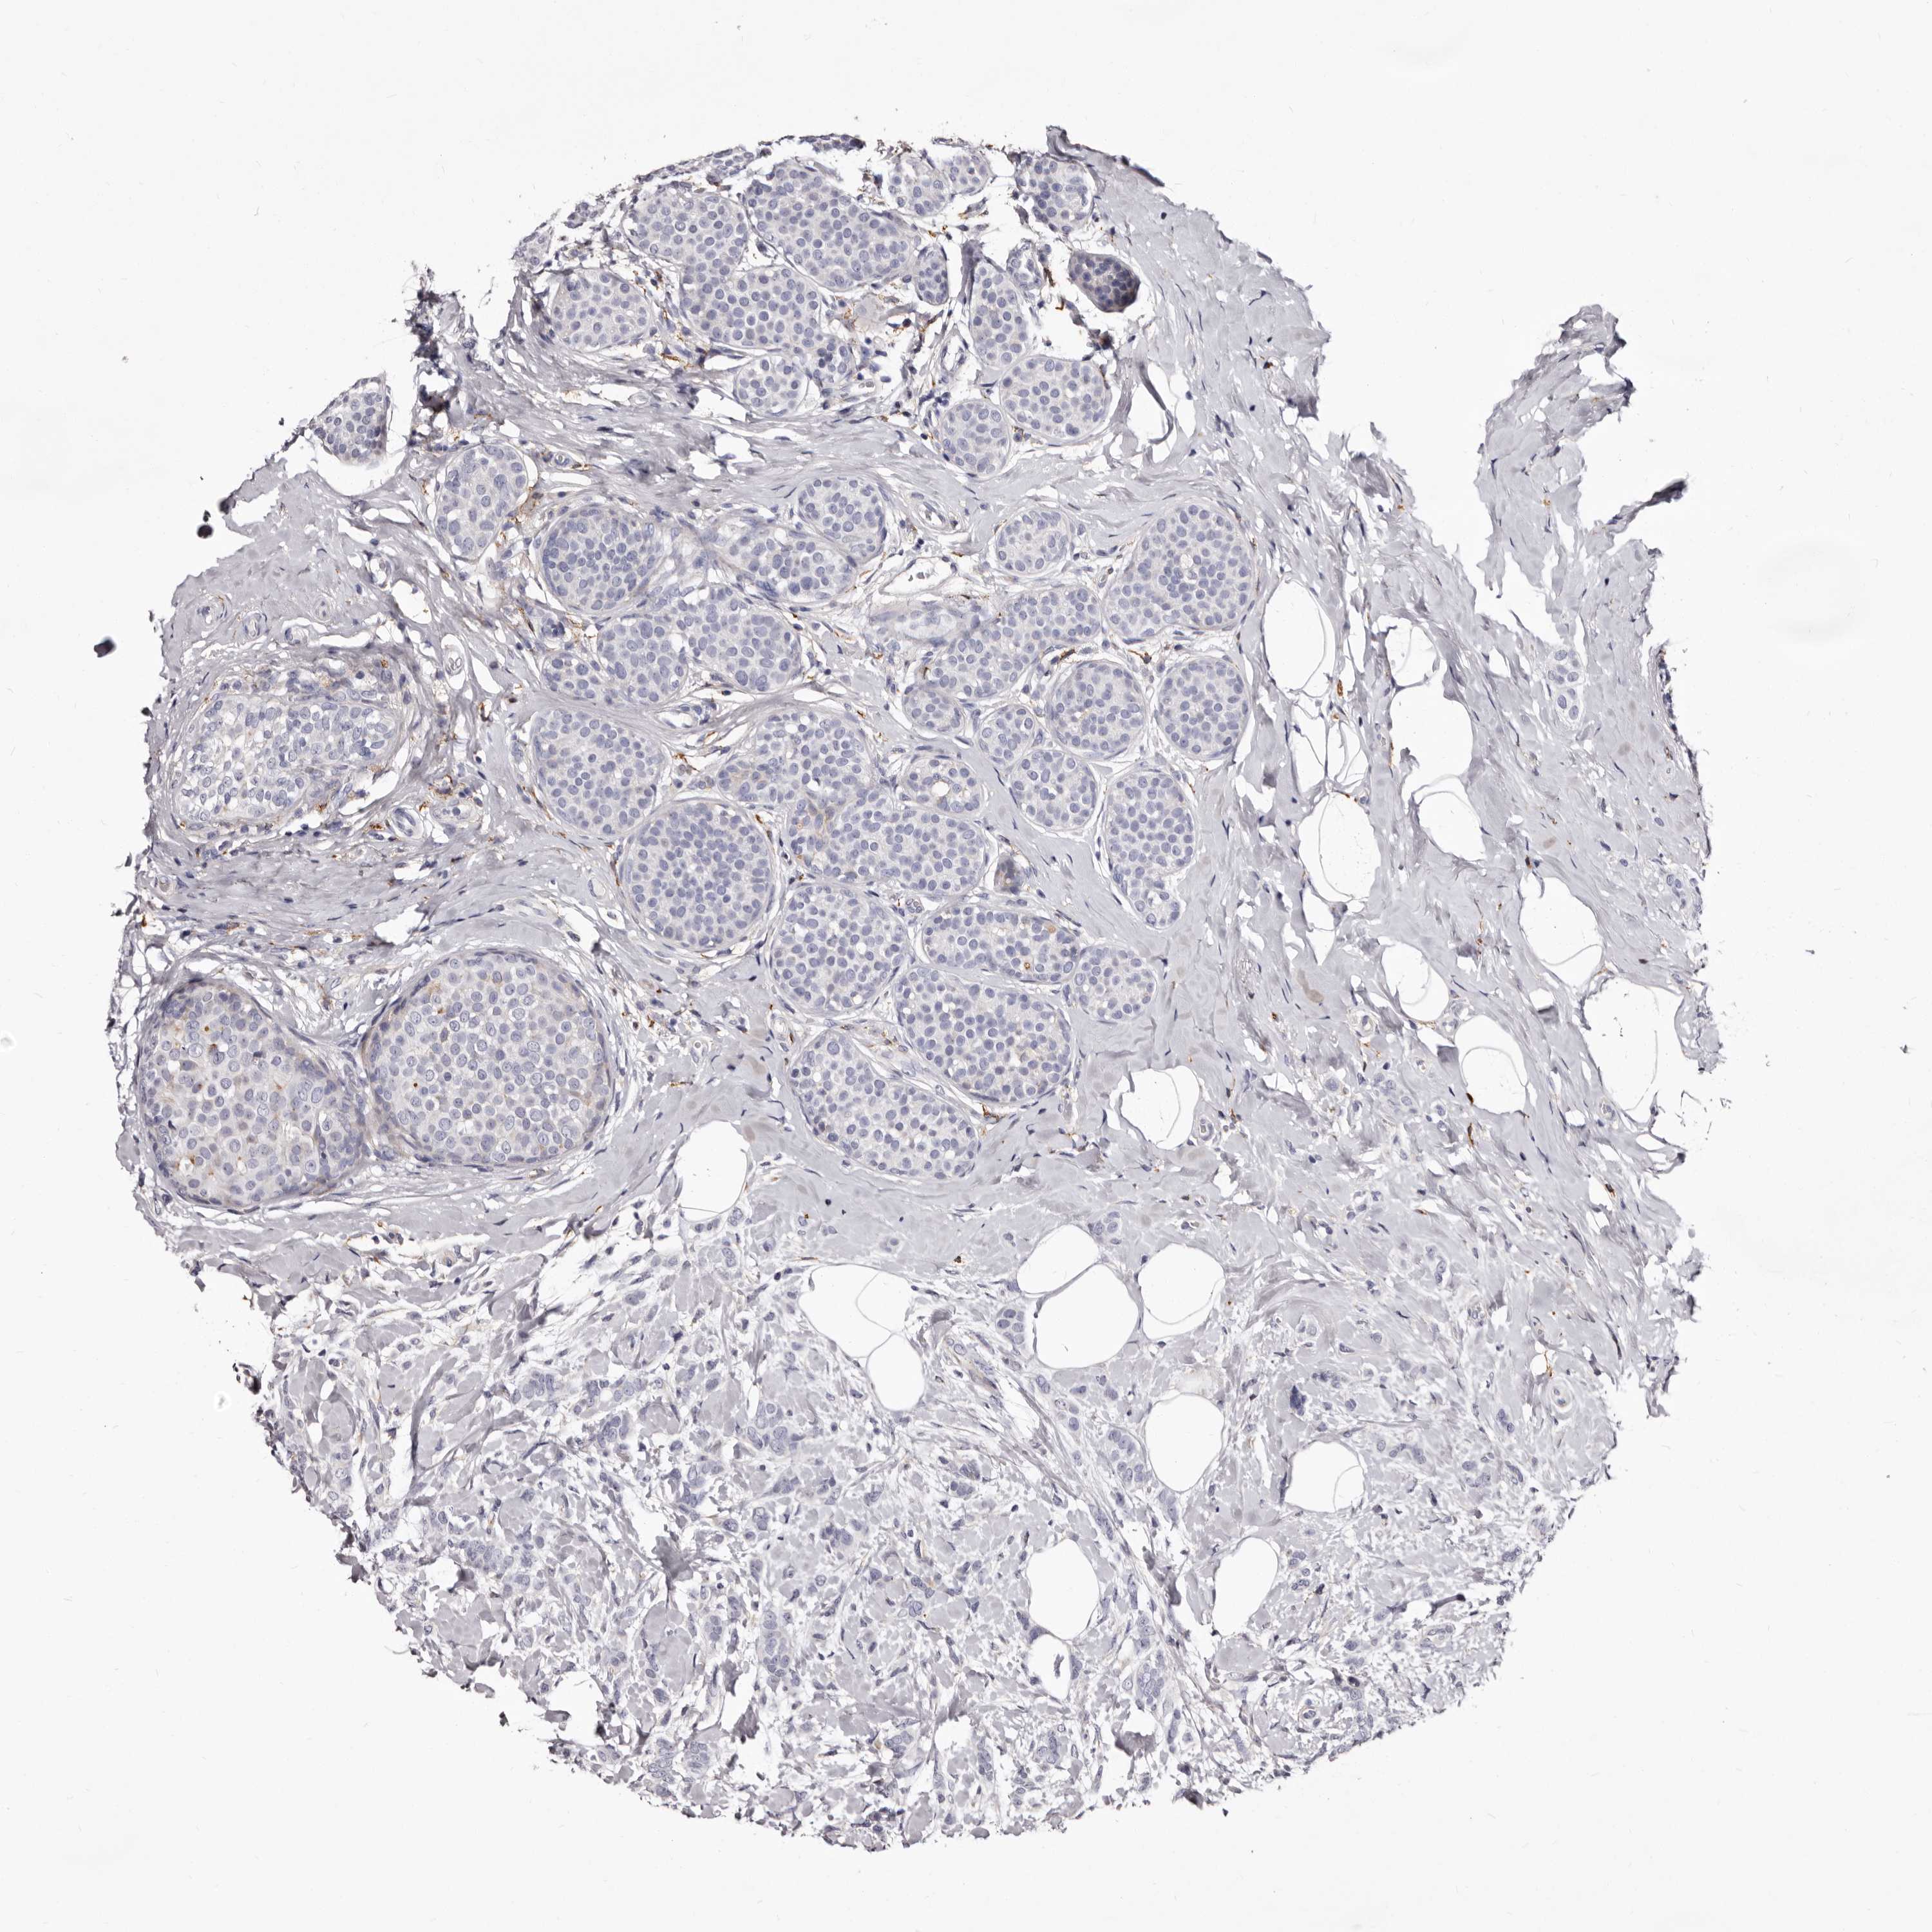

CANCER BREAST CANCER Show tissue menu

BRCA TCGA BRCA VALIDATION PROTEIN EXPRESSION

ANTIBODIES

AND

VALIDATION